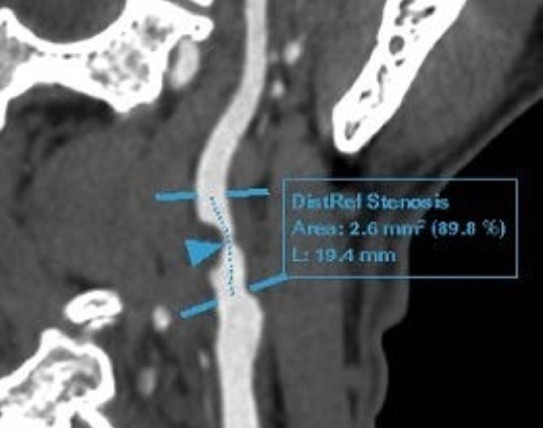

Phim chụp tổn thương của bệnh nhân.

Các kết quả siêu âm và chụp cắt lớp mạch máu não cho thấy ông Đ. bị hẹp nặng 90% gốc động mạch cảnh trong phải do mảng xơ vữa hỗn hợp, kèm theo lóc tách nhỏ gốc động mạch cảnh trong trái với núm phình nhỏ. Mảng xơ vữa cũng lan tỏa ở nhiều đoạn mạch khác như động mạch dưới đòn và xoang hang. Chụp CT động mạch vành ghi nhận xơ vữa vôi hóa nhẹ, gây hẹp 30-40% các nhánh động mạch vành.